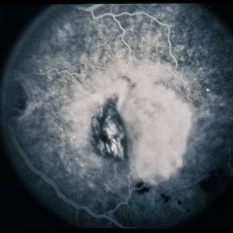

RPE Tear

RPE Tear

Sep 9 2014 by David Callanan, MD

78-year-old male, RPE tear.

Condition/keywords: retinal pigment epithelium